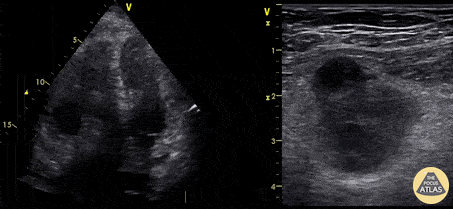

Right Ventricular Dysfunction - Clot in Transit & Femoral DVT

A 73 year old male presented with several day history of moderate dyspnea as well as right LE discomfort. POCUS identified both a right intracavitary thrombus as well as right femoral phlebitis. He was treated with heparin for both. Pierre Bernatas, @pb2316 Emergency Physician. Limousin, France.